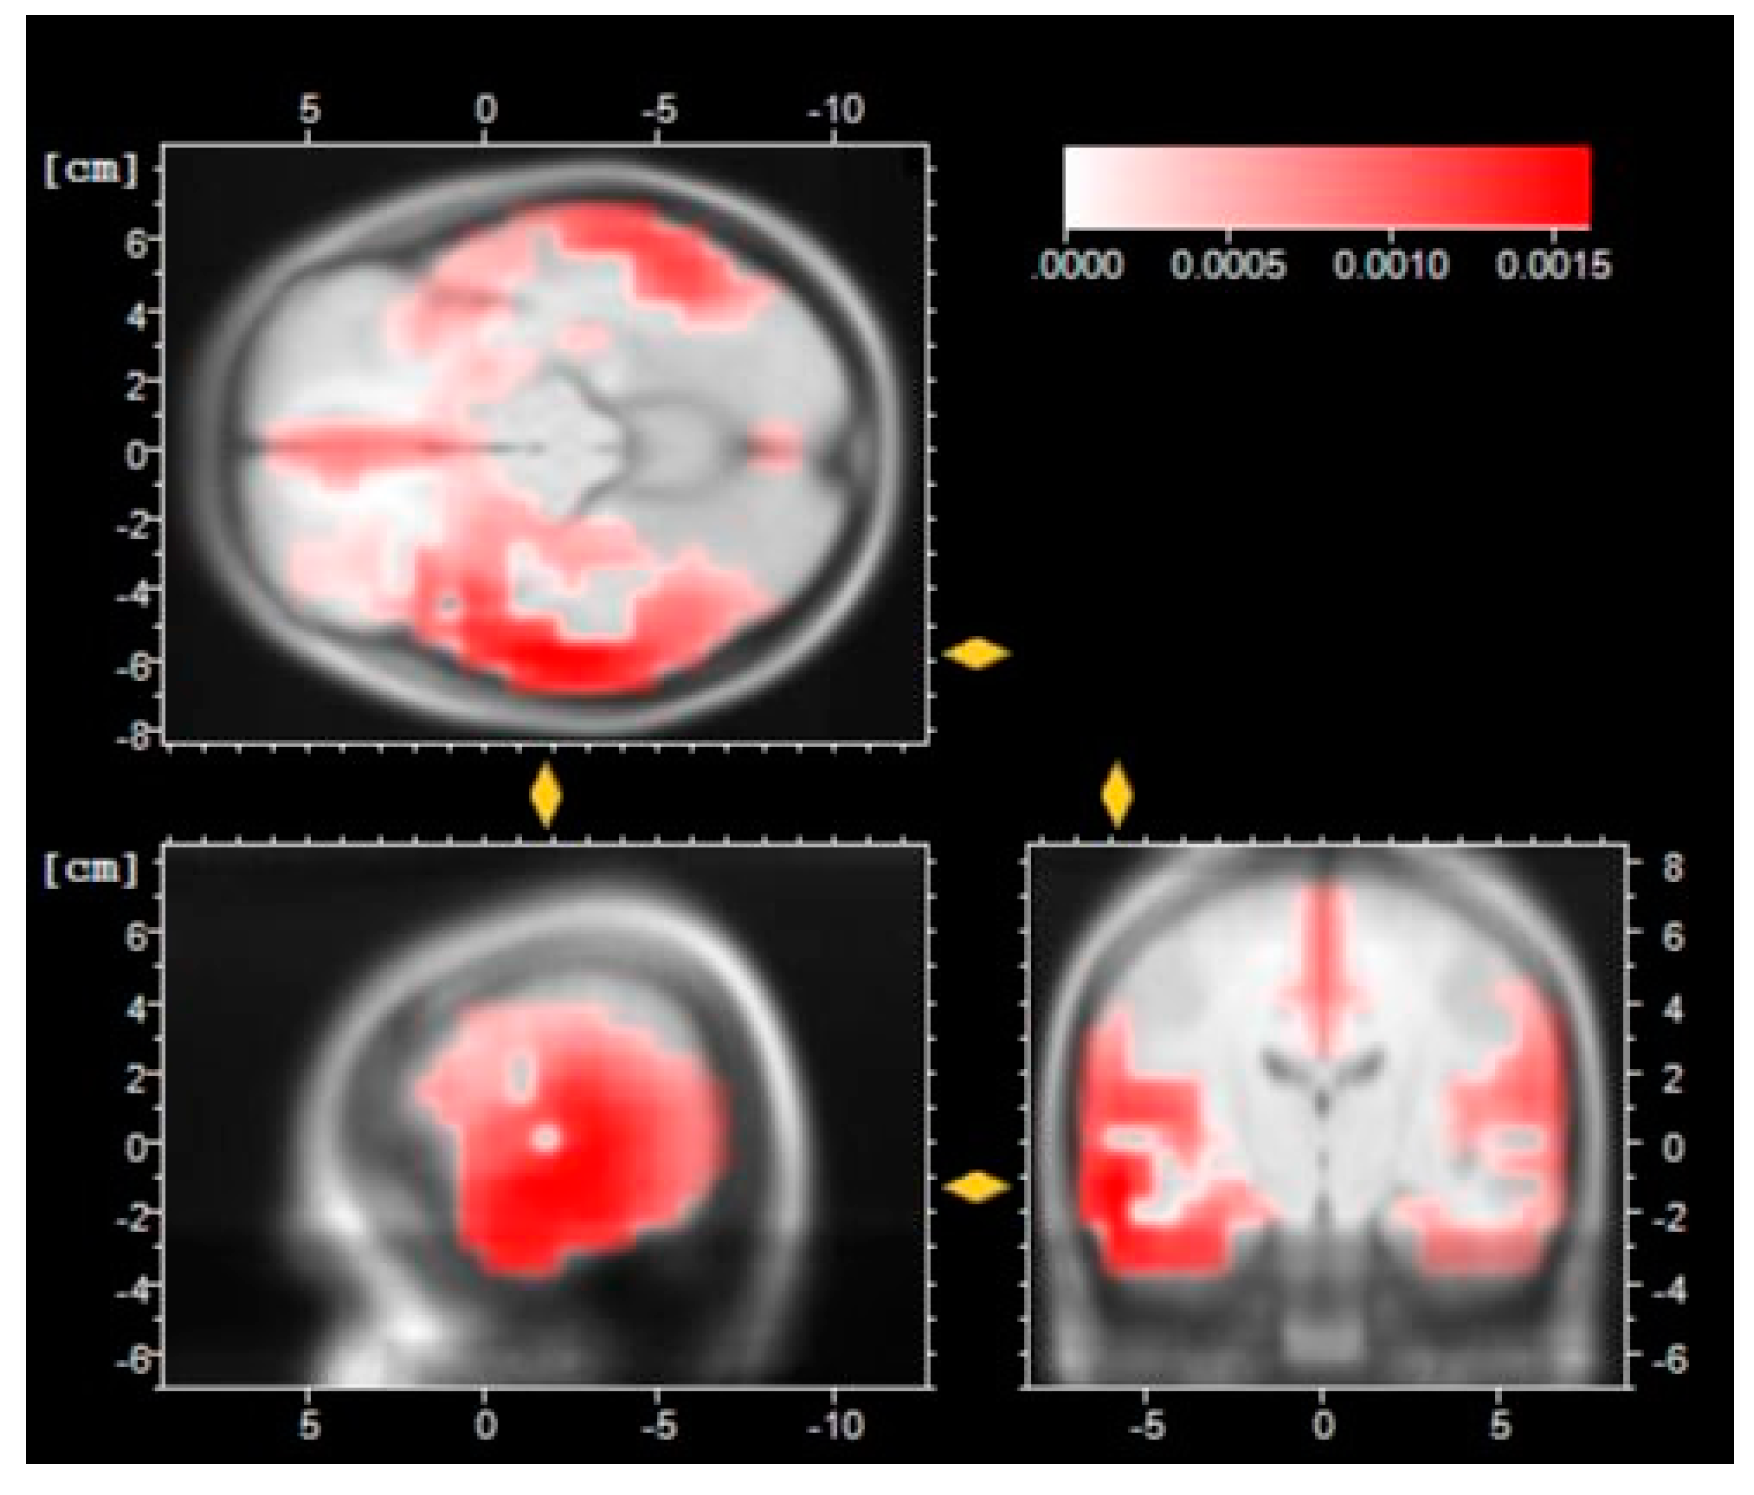

- Pascual-Marqui, R.D.; Esslen, M.; Kochi, K.; Lehmann, D. Functional imaging with low-resolution brain electromagnetic tomography (LORETA): A review. Methods Find. Exp. Clin. Pharm. 2002, 24 (Suppl. C), 91–95. [Google Scholar]